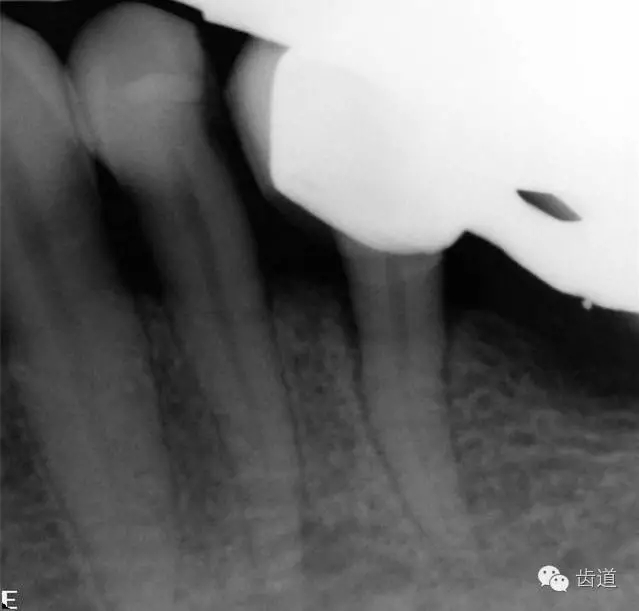

2、45,46術(shù)前片顯示根管上段充填物,根管影像不清晰,少許根尖暗影

1、45,46牙體缺損,慢性根尖周炎(不良根管治療術(shù)后)

45,46去除原充填物和齲壞,揭全髓室頂,46探及近頰近舌遠(yuǎn)中三根管,45單根管,超聲輔助清理髓腔及根管,去除根管內(nèi)充填物,根管下段細(xì)小堵塞欠通暢,8號/10號C銼疏通根管,pathfile+protaper鎳鈦根管預(yù)備,熱牙膠根管充填。